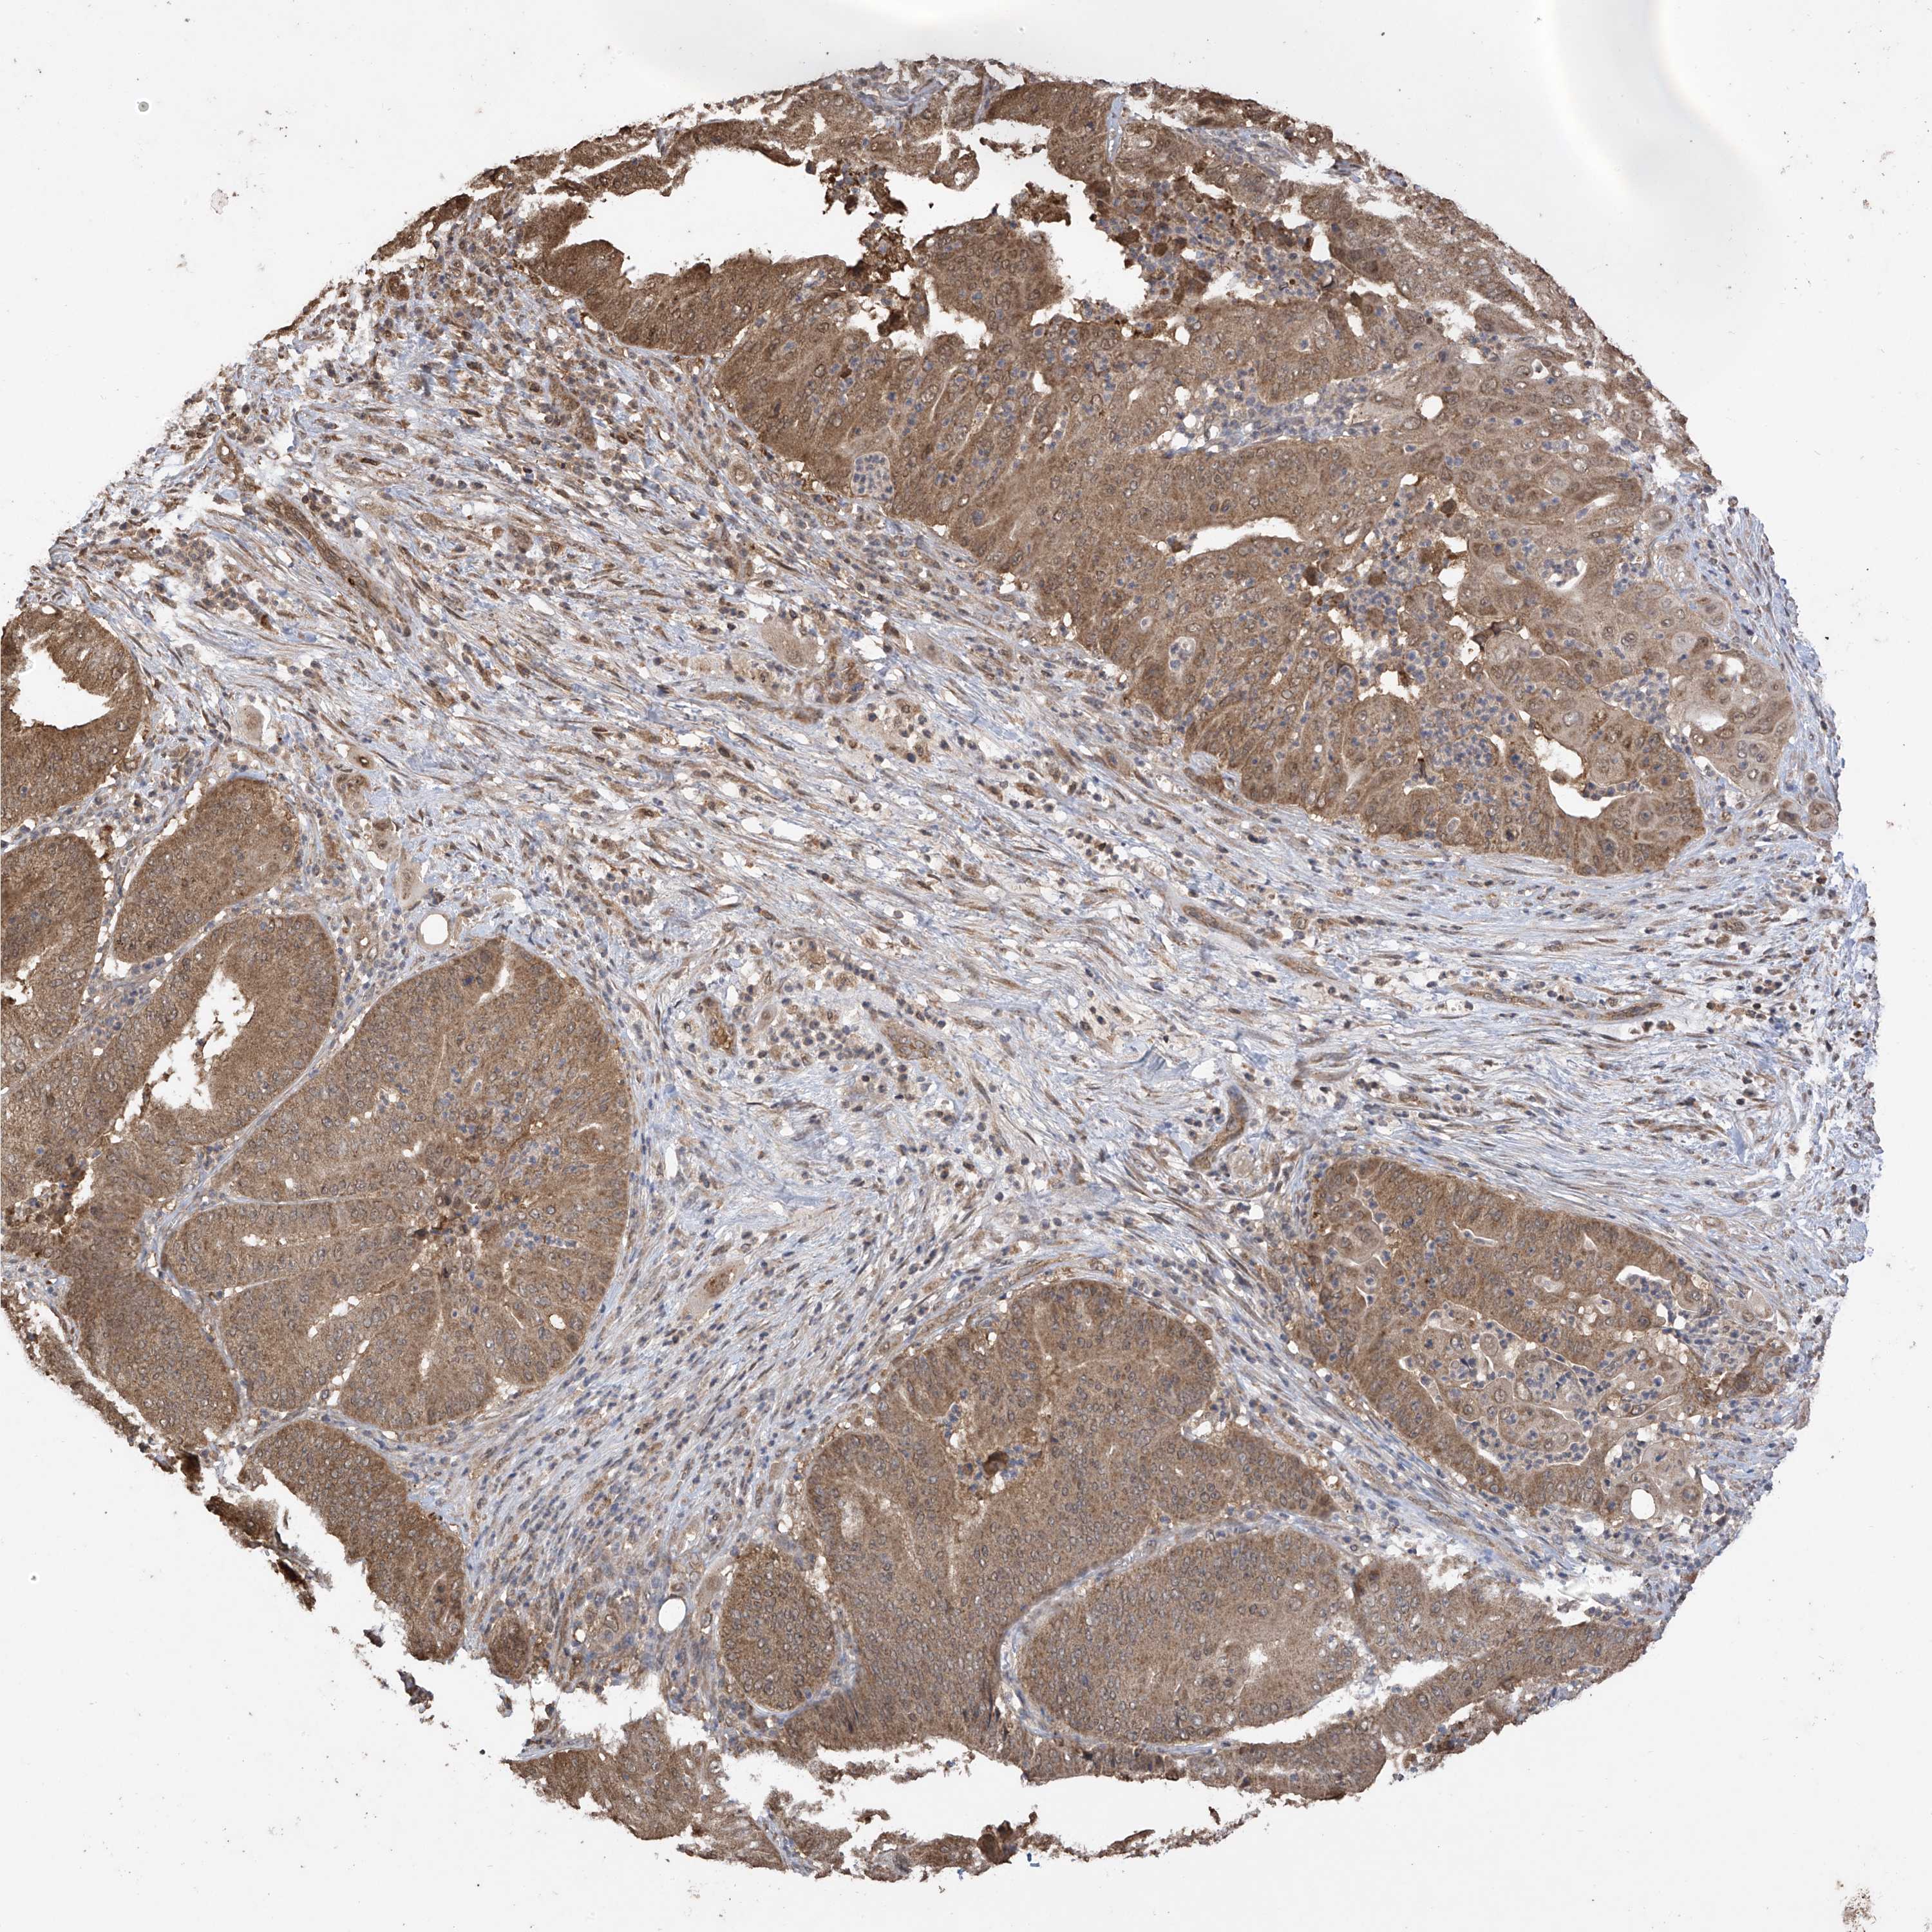

PANCREATIC CANCER - Protein expressioni

A mouse-over function shows sample information and annotation data. Click on an image to view it in a full screen mode. Samples can be filtered based on level of antibody staining by selecting one or several of the following categories: high, medium, low and not detected. The assay and annotation is described here.

Note that samples used for immunohistochemistry by the Human Protein Atlas do not correspond to samples in the TCGA dataset.

Antibody stainingi

Antibody staining in the annotated cell types in the current human tissue is reported as not detected, low, medium, or high, based on conventional immunohistochemistry profiling in selected tissues. This score is based on the combination of the staining intensity and fraction of stained cells.

Each image is clickable and will lead to virtual microscopy that enables deeper exploration of all samples and also displays staining intensity scores, fraction scores and subcellular localization as well as patient and tissue information for each sample.

Antibody HPA034602

Antibody HPA034603

Antibody CAB033424

Staining

High

Medium

Low

Not detected

Intensity

Strong

Moderate

Weak

Negative

Quantity

>75%

75%-25%

<25%

None

Location

Nuclear

Cytoplasmic/membranous

Cytoplasmic/membranous,nuclear

Adenocarcinoma, NOS